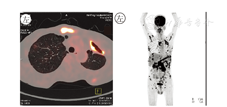

患者于2016年7月中旬出现双侧乳房增大,2016年7月28日再次入院。近1年体质量由57 kg下降至45 kg。既往史:2015年5月因右下腹痛于当地医院诊断肠套叠,行右半结肠切除术,术后病理示:炎性改变。2015年7月因发热、胸痛于当地医院诊断肺脓肿,行左胸左上肺叶切除术,术后病理示:大量纤维组织增生,多灶性化脓性炎,符合脓胸改变。体格检查:患者生命体征平稳,慢性病面容,体型消瘦,身体质量指数(BMI)=17.3 kg/m2;双侧乳房稍增大,左侧乳房区触及大小1.5 cm×1.0 cm包块,压痛阳性,活动度欠佳,与周围组织无黏连;左胸可见一长约20 cm术后瘢痕,右侧腹部可见一长约15 cm纵行手术瘢痕,左侧胸部及双侧肋骨压痛阳性;腹部平软,无压痛及反跳痛,肝、脾肋下未触及。2016年7月入院后实验室检查:白细胞计数12.52×109/L,中性粒细胞计数8.93×109/L,Hb 114 g/L;红细胞沉降率90 mm/1 h,降钙素原0.070 g/L,C反应蛋白54.7 mg/L;铁蛋白508.50 g/mL,β2-微球蛋白2.57 mg/L;真菌D-葡聚糖54.82 mg/L;卵泡刺激素48.25 IU/L(正常值1.5~12.4 IU/L),黄体生成素37.47 IU/L(正常值1.7~8.6 IU/L),催乳素42.88 g/L(正常值4.04~15.2 g/L),雌二醇、雌三醇、孕酮、睾酮、生长激素、促甲状腺素、促肾上腺皮质激素、皮质醇未见异常。乳腺B超示:左侧乳头旁9点钟位置见一1.6 cm×1.0 cm低回声区,形态不规则,边界不清楚。垂体MRI提示垂体肉芽肿性炎性反应。2016年8月3日复查PET-CT示:考虑结核或者其他感染性病变可能,其中左肺上叶、左侧腰大肌代谢相对上次(2016年5月7日)病灶稍缩小,双肺门、纵隔内、右侧膈肌脚深面、中上腹部腹膜后区多个淋巴结、吻合口后方系膜及升结肠旁系膜内多个结节及全身多次骨骼代谢相对上次增高(图4)。右侧髂骨高代谢病灶病理检查示:肉芽肿性炎伴凝固性坏死及化脓性炎,考虑结核或非典型分枝杆菌(nontuberculous mycobacteria,NTM)感染(图5)。病理组织培养示:无细菌生长。入院继续予抗结核治疗,患者症状无明显缓解,考虑NTM可能性大,予经验性加用克拉霉素治疗,建议患者进一步行组织涂片、培养及PCR明确病原学,患者拒绝,带药出院继续治疗。2017年6月12电话随访患者全身无明显疼痛,症状明显好转。

注:全身多处高代谢病灶,考虑结核或其他感染性病变(标准摄取最大值为18,平均值为3.6~6.8)